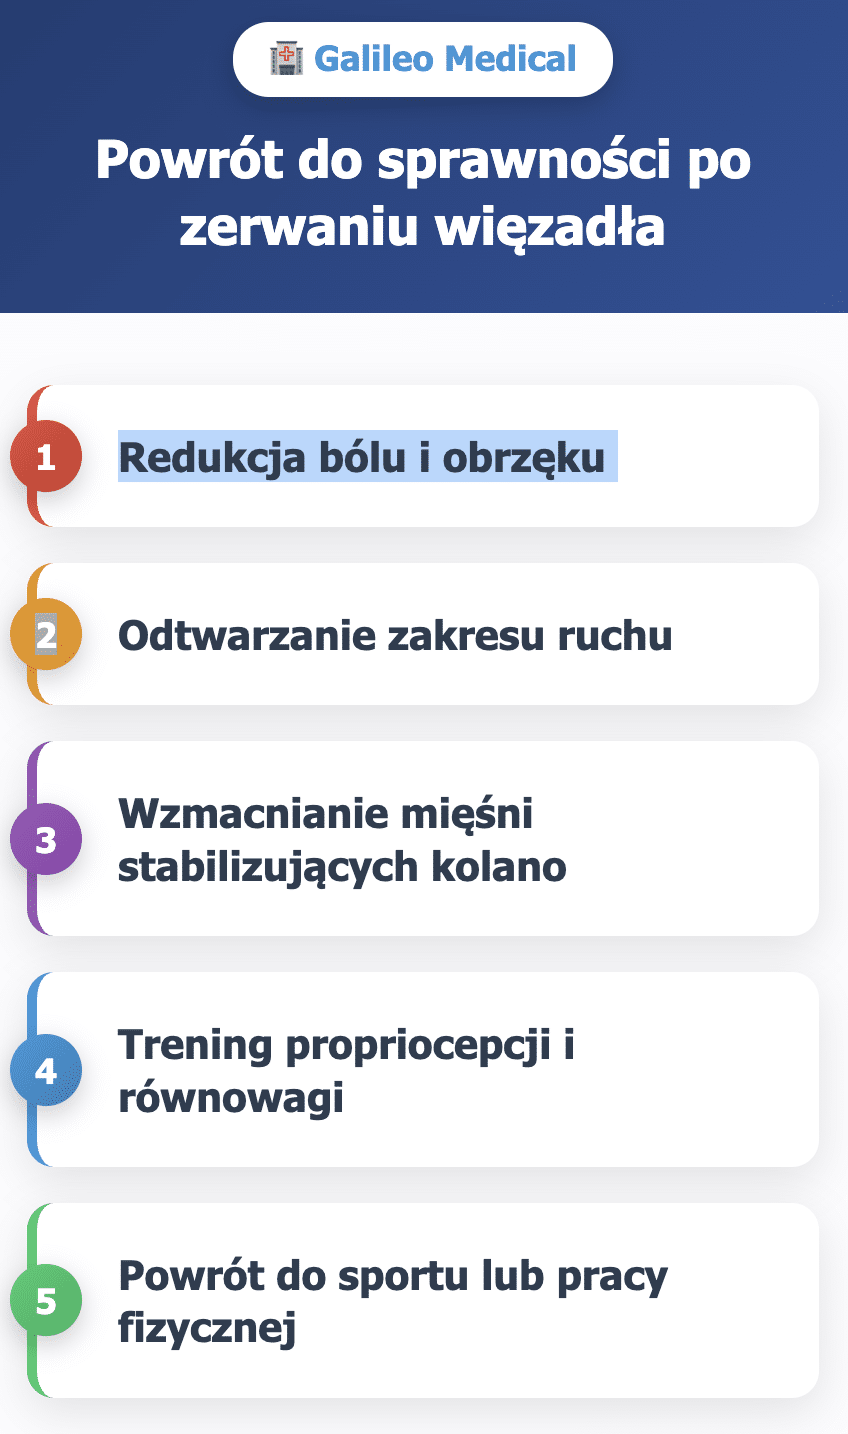

Rehabilitacja po zerwaniu więzadła w kolanie krok po kroku z Galileo Medical

Powrót do sprawności po zerwaniu więzadła to proces wieloetapowy, który w Galileo Medical prowadzony jest przez zespół fizjoterapeutów i lekarzy specjalizujących się w urazach kolana. Każdy pacjent ma indywidualny plan usprawniania od pierwszych dni po urazie aż do powrotu do sportu lub aktywności zawodowej.

- Redukcja bólu i obrzęku. W pierwszych dniach najważniejsze jest zmniejszenie stanu zapalnego. Wykorzystujemy krioterapię, czyli zimne okłady i zabiegi chłodzące, a także odpowiednie ułożenie kończyny i pomoc kul łokciowych. W razie potrzeby pacjent konsultowany jest z ortopedą pod kątem farmakoterapii.

- Odtwarzanie zakresu ruchu. Fizjoterapeuci wprowadzają mobilizacje stawowe oraz ćwiczenia bierne, które z czasem przechodzą w czynne ruchy bez obciążenia. To zapobiega przykurczom i sztywności.

- Wzmacnianie mięśni stabilizujących kolano. Wprowadzamy ćwiczenia izometryczne i oporowe – z taśmami, stepem, ciężarem własnego ciała. Szczególną uwagę przykładamy do mięśnia czworogłowego, grupy kulszowo-goleniowej i łydki.

- Trening propriocepcji i równowagi. Ćwiczenia na niestabilnym podłożu (np. poduszki sensomotoryczne, bosu) uczą ciało właściwej reakcji na bodźce. Już na tym etapie wdrażamy funkcjonalny trening medyczny, który imituje codzienne ruchy lub obciążenia związane z daną aktywnością fizyczną.

- Powrót do sportu lub pracy fizycznej. Programy Galileo Medical obejmują treningi dynamiczne: jazdę na rowerze, marszobieg, ćwiczenia skocznościowe i koordynacyjne. Powrót do pełnych obciążeń następuje dopiero po pozytywnych testach funkcjonalnych – nie wcześniej.

W całym procesie dbamy nie tylko o kolano, ale i o edukację pacjenta: uczymy bezpiecznych nawyków ruchowych, rozgrzewki i wzmacniania całej kończyny dolnej. Dzięki temu minimalizujemy ryzyko nawrotu kontuzji.